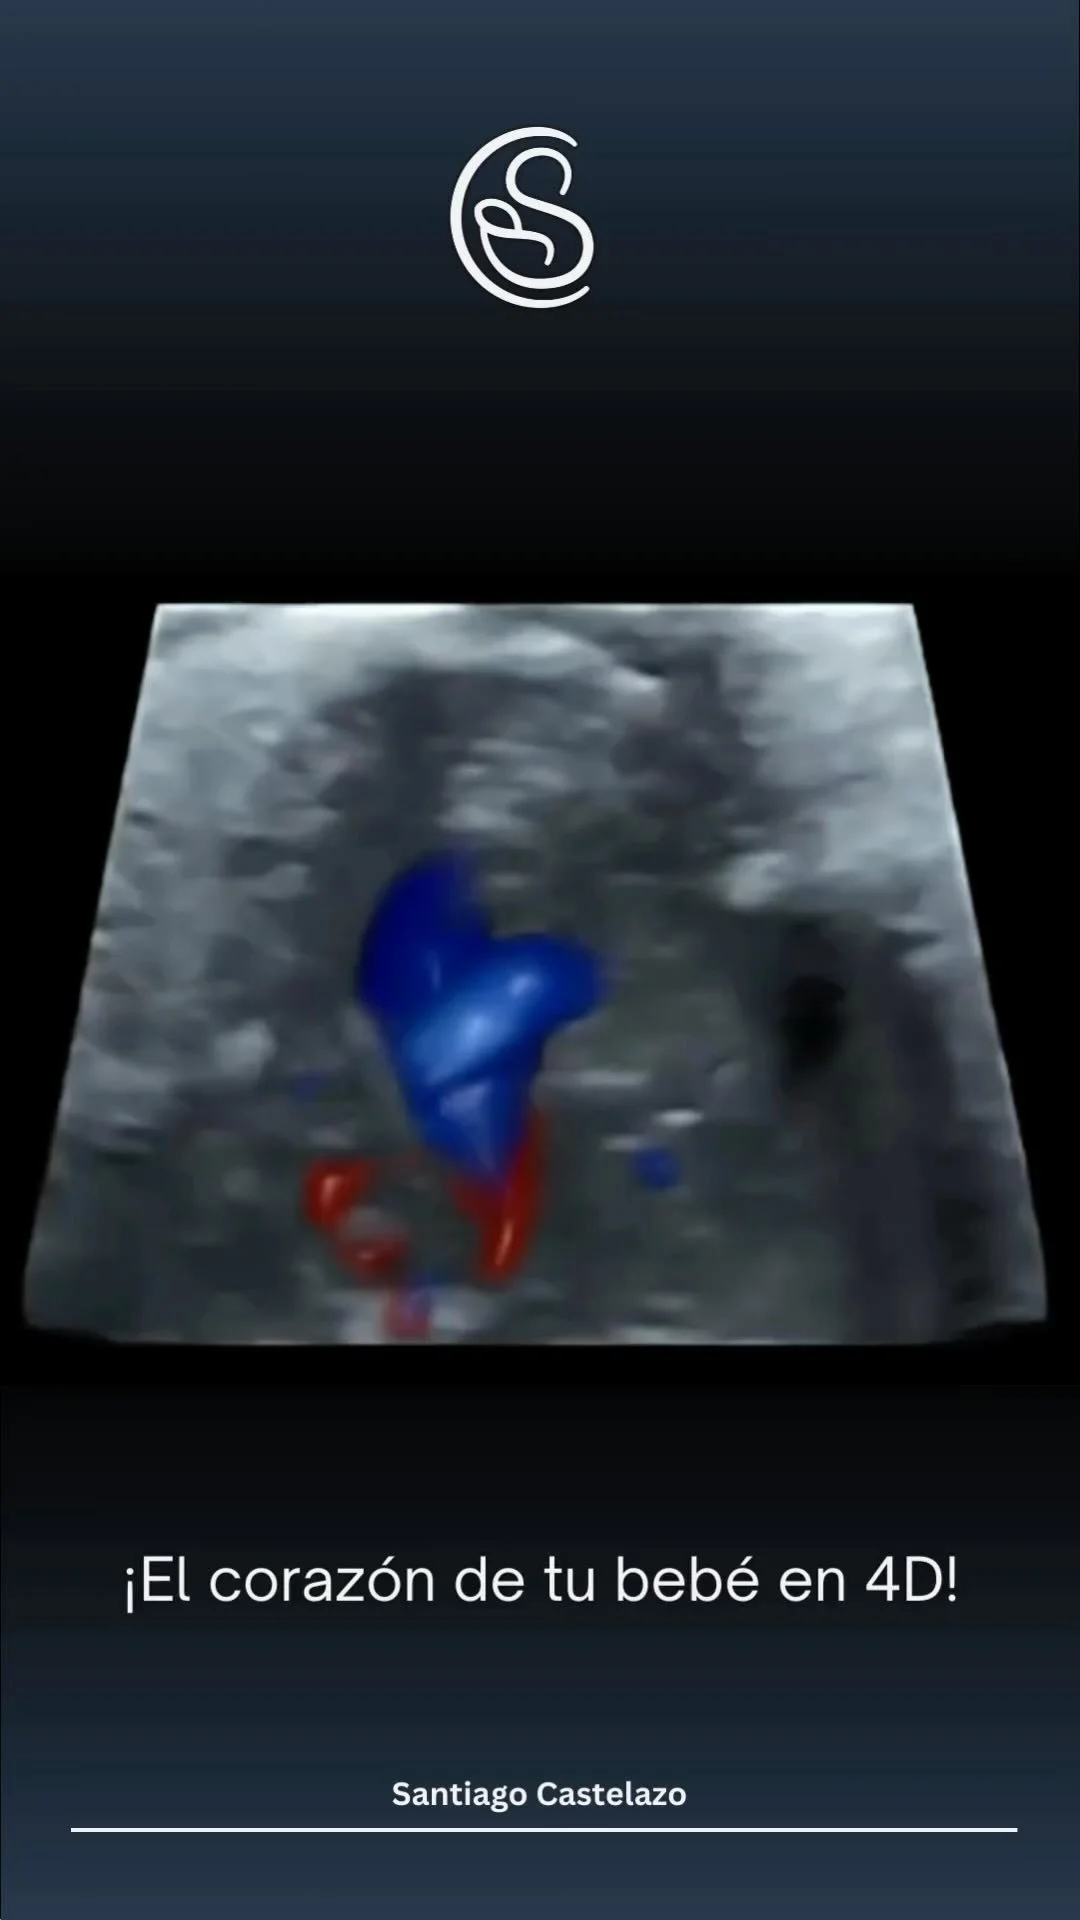

La Medicina Materno Fetal es una rama subespecializada de la Ginecología y Obstetricia que se enfoca en cuidar tanto a la madre como al bebé durante el embarazo. Mi experiencia en esta área me permite brindar un cuidado integral y personalizado a cada paciente. Utilizo tecnologías avanzadas, como el ultrasonido, para monitorear el desarrollo del bebé y detectar cualquier problema potencial en cada trimestre del embarazo.